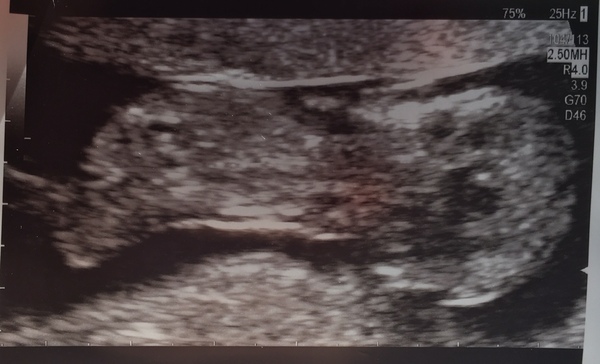

Had my 12wk scan this morning, all good! nuchal measurement of 2mm, and everything else present and correct! The baby was being a bit lazy and she had to poke it a few times!

I was worried because of my fat belly, but she (possibly quite politely) didn't mention it, so it obviously wasn't TOO much of an issue thankfully!

Just got to wait for the blood results now before we tell anyone else... but I'm so happy there was a wriggly baby in there!

Here's a pic of the slightly squashed alien (scanner was pressing down and poking it at the time!)